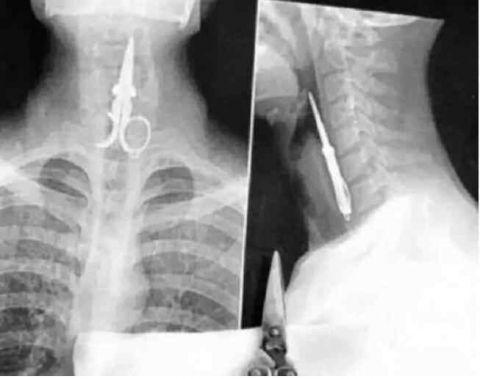

又是打架时候干的,不过这人现在康复了